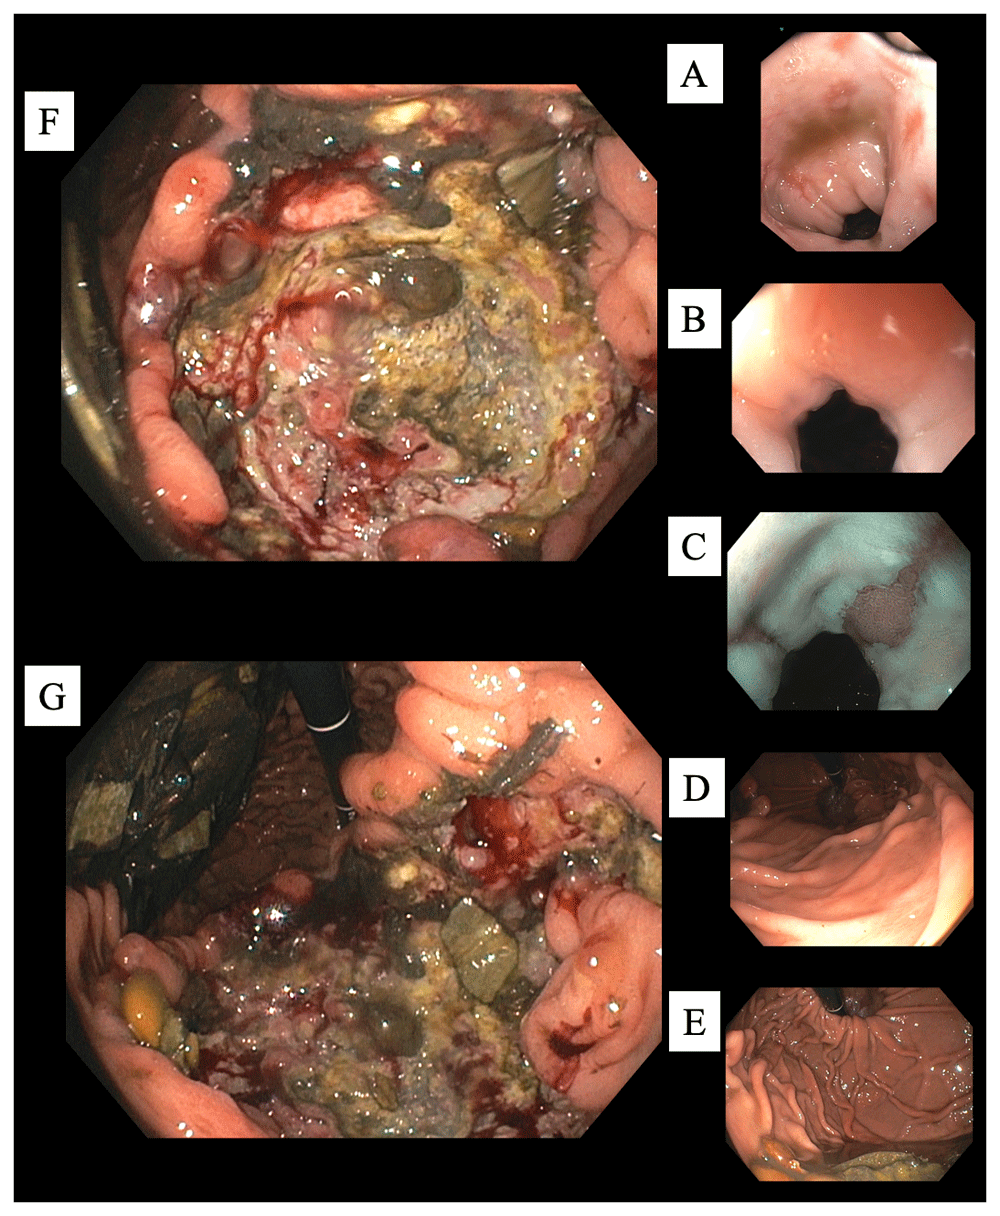

Vital signs and measurements were unremarkable. A detailed physical examination was nonrevealing. Serum laboratory analysis was notable for a significant anemia, as well as a low vitamin B12 and iron deficiency (Table 1). She was urgently managed with a restrictive transfusion strategy by one unit of leukoreduced packed red blood cells, which improved her symptoms and hemoglobin. Abdominopelvic imaging was obtained by computerized tomography (CT) scans with contrast, which were primarily equivocal (Figure 1). Subsequently, she underwent esophagogastroduodenoscopy (EGD) for further evaluation. Esophageal findings included moderate esophagitis and salmon-colored mucosa at the gastroesophageal junction suggestive of Barrett's esophagus. Beyond the esophagus, a large 7-cm hiatal hernia was evident. An extensive, deep ulcer was noted to involve the entirety of the incisura and pre-pyloric area, as well as extended along the lesser curvature (Figure 2). Multiple biopsies of the ulcer were obtained to evaluate for malignancy, as well as random gastric biopsies to evaluate for Helicobacter pylori colonization. Helicobacter pylori immunohistochemical (IHC) stain was ultimately negative. Due to the tumor's size, gross appearance, ulcerations, and bleeding erosions noted on EGD a malignant process was suspected. Based on the suspicions for an underlying malignant gastric neoplasm and the presence of a vitamin B12 deficiency, serum serologic testing for PA was obtained. Laboratory testing was positive for anti-IF confirming the diagnosis of PA (Table 1).

(From proximal to distal.) (A) Esophagitis. (B) Gastro-esophageal junction. (C) More esophagitis, and a tongue of columnar mucosa. (D) Normal gastric cardia. (E) Normal gastric fundus. (F) Cavernous ulcer along the incisura (lesser curvature) with debris, food particles, and some central exudates (G) Continued ulcer description. At the 12 o'clock position the scope is originating from the gastric cardia and fundus region. At 3 o'clock is the expected location of the pylorus. However, due to size and extent of the ulcer typical anatomy and landmarks were considerably distorted making visualization of the fundus from that particular EGD position not possible. At 6 o'clock the ulcer is shown to extend along the incisura. At 9 o'clock food debris is seen along the greater curvature.